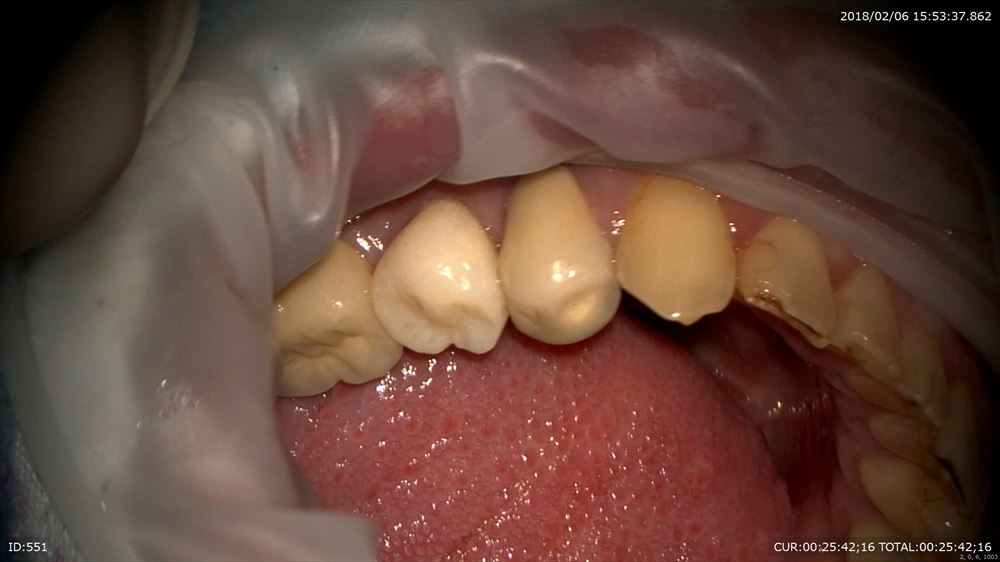

今日は矯正の装置を外した女の子。外してとても喜んで頂けました。

術前。あらま。

今日

リテーナー使ってねー。